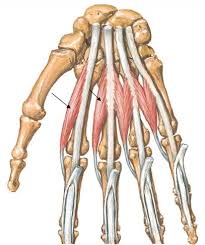

1181 × 1300 - gimolimpo.com

{"id":"Rohz-pKMmS4_0M:","isu":"gimolimpo.com","itg":0,"ity":"jpg","oh":1300,"ou":"http://www.gimolimpo.com/PAGINA%2062/musculosdorsales.jpg","ow":1181,"pt":"ANATOMIA

HUMANA","rid":"KhRkfq-OMAvQ7M","rmt":0,"rt":0,"ru":"http://www.gimolimpo.com/Paginas/ANATOMIA%20HUMANA.htm","s":"Visión

Frontal","sc":1,"th":236,"tu":"https://encrypted-tbn0.gstatic.com/images?q\u003dtbn:ANd9GcQbfHPY9kAjUYom1KfJZWZndoE6JCieaUeZv2ENDRKwDT_ucpXeRQ","tw":214}